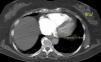

Para além da avaliação da carga embólica na TCMD, foram efetuadas medições quantitativas dos diâmetros das estruturas vasculares (VCS e VA) e cardíacas (VD, VE, ratio VD/VE; SC, AP, Ao, ratio Ap/Ao) relacionadas com a árvore pulmonar. O desvio do SIV e o refluxo de contraste na veia cava inferior (VCI) foram avaliados qualitativamente, de forma a definir os sinais de DVD (Figuras 2-5).

Na angio-TC, o grupo B apresentou diâmetros do VD, ratio VD/VE (p-0,002), VCS, VA e SC superiores. Os diâmetros da AP e o ratio AP/aorta foram semelhantes.

Na angio-TC, o QS correlacionou-se linearmente com os parâmetros de DVD avaliados (diâmetros do VD, VCS, VA e SC; ratio VD/VE e AP/Ao; percentagem de sobrecarga no SIV e de refluxo na VCI), conferindo à carga embólica avaliada por QS um potencial multiparâmetros que ainda não se encontrava descrito na literatura.